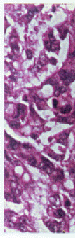

1、3、5代移植瘤形态相似。瘤细胞呈巢状分布有腺 腔样结构,瘤细胞大小不等,多为柱状,核分裂相 多见,可见癌细胞向细胞外分泌粘液,符合结肠高 分化腺癌的特点,见图1。

图1 第5代移植瘤组织,瘤细胞呈巢状分布,有腺腔样结构,瘤细胞大小不等,多为柱状,核分裂相多见,可见瘤细胞向细胞外分泌粘液(HE×400)

Fig1 The fifth generation of xenografted tumor.The tumorous cells distributed like nest,with column shape,inconsistent size and glandular cavity structure,and secreted mucus.Nuclear fission was common (HE×400)